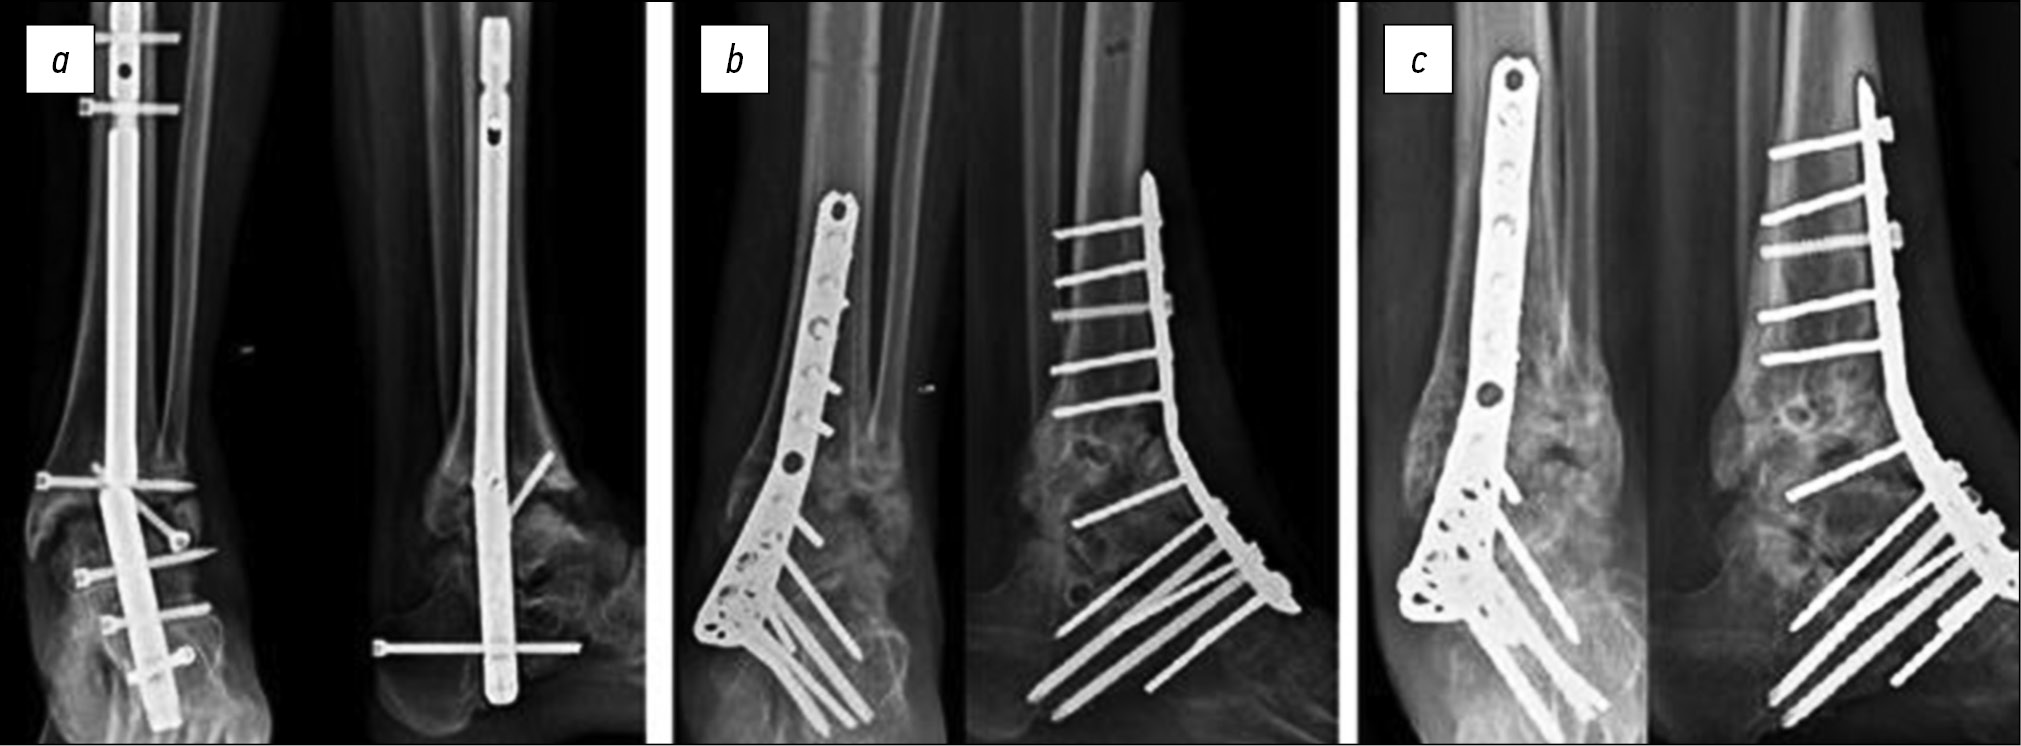

Больная Е., 36 лет, госпитализирована для осуществления ревизионного оперативного вмешательства через 9 месяцев после выполнения первичной операции с жалобами на интенсивный болевой синдром, ограничивающий возможность опоры на оперированную конечность. При обследовании выявлено, что на фоне асептического расшатывания элементов интрамедуллярного фиксатора сформировались нестабильность фиксации, диастаз между таранной и большеберцовой костями, очаговые дефекты костной ткани. Были выполнены удаление ранее установленной металлоконструкции, обработка суставных поверхностей до кровоточащей кости, реостео-синтез накостной пластиной с угловой стабильностью винтов, пластика дефектов аллогенной костной крошкой (рис. 1).

Рис. 1. Рентгенограммы больной Е.: a — через 9 месяцев после первичного оперативного вмешательства, b — после ревизионного оперативного вмешательства, c — через 6 месяцев после ревизионного оперативного вмешательства

Fig. 1. Radiographs of patient E.: a — 9 months after her first surgery, b — the revision surgery, and c — 6 months after the revision surgery